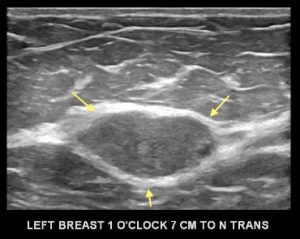

Maybe you were wondering about the smaller mammographic mass that is posterior to the dominant mass. Here is the ultrasound of that second mass:

What is this mass?

C. Lymph Node

Explanation: This is the normal sonographic appearance of an intramammary lymph node, with a thin hypoechoic cortex and a hyperechoic fatty hilum.